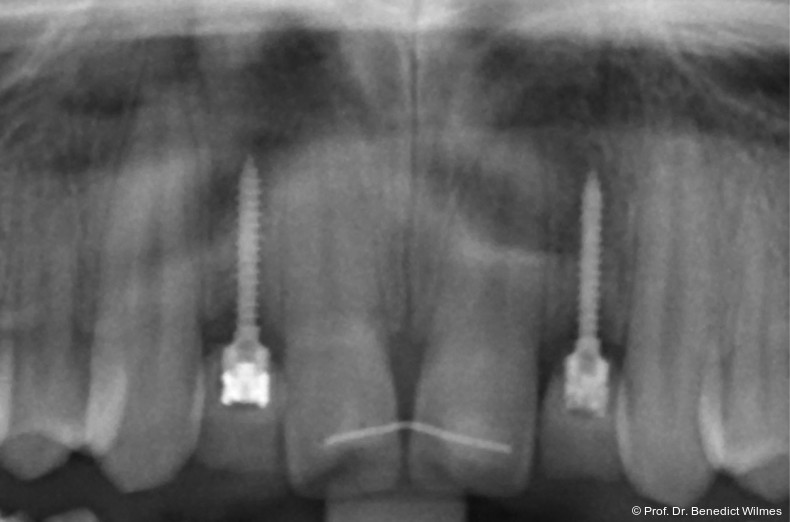

Ein 14-jähriger Patient wurde bei Aplasie der beiden oberen seitlichen Schneidezähne mit dem Ziel der beidseitigen Lückenöffnung kieferorthopädisch therapiert (Abb. 1a+b). Zum Ende der kieferorthopädischen Behandlung wurden zwei Miniimplantate in Regio 2er als temporärer Zahnersatz inseriert (Benefit System, PSM, 2 x 13 mm, Abb. 2a+b). Nach Abdrucknahme wurden Kronen auf den Peek-Abutments modelliert und diese mit Kunststoff auf die Abutments geklebt (Abb. 3a–d). In den Abbildungen 3 und 4 sind die klinischen und röntgenologischen Nachkontrollen innerhalb der nächsten achteinhalb Jahre dokumentiert. Man erkennt einen sowohl in der Höhe als auch in bukkopalatinalen Breite verbleibenden gesunden Knochen ohne Anzeichen einer Atrophie. Im Alter von 23 Jahren wurden die definitiven Implantate ohne die Notwendigkeit einer Augmentation eingesetzt (Abb. 5) und nach Einheilung prothetisch versorgt (Abb. 6a–e und Abb. 7a–c).